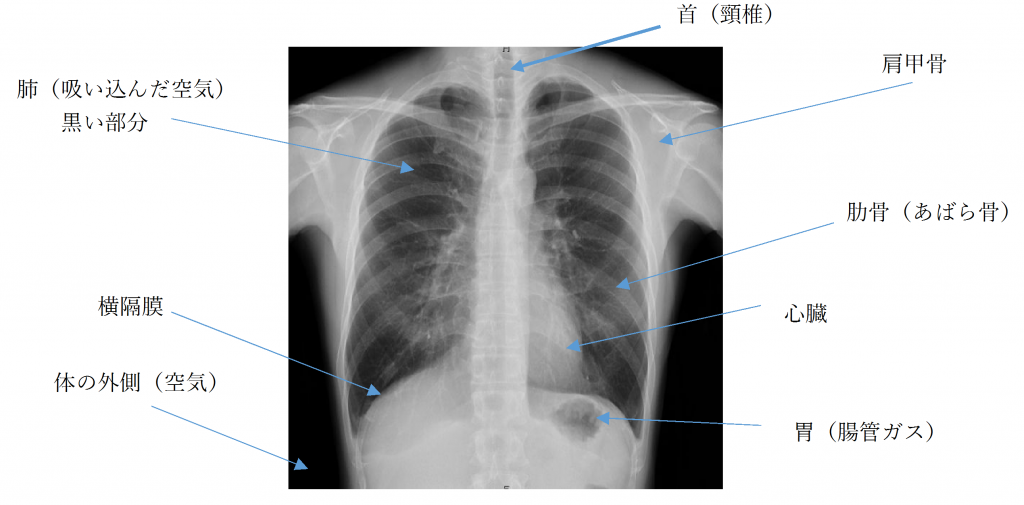

健康診断の際に必ず撮影する胸部X線検査ですが、実際に何が写っているかご存知でしょうか。下の画像に記載してあるように、骨や肺、心臓などが白黒の画像として撮影されています。胸部X線検査では、肺がん・肺炎等を早期に見つける事が目的の検査となっています。

画像のように胸部X線画像には骨が写ることから、首の辺りにはアゴが、肺の上部には 肩甲骨が重なってしまいます。初期の肺がんは小さく、淡く見えるため、比較的はっきりと見える骨と重なってしまうと隠れて見えにくくなります。また下着の金具、プラスチック等も骨以上にはっきりと白く見えてしまいます。肺の上部(肺尖)は画像上の異常が見つかることが多いとされる部位であり、診断に影響が出ることから、骨をできる限り肺と重ならないようにすることが大切です。